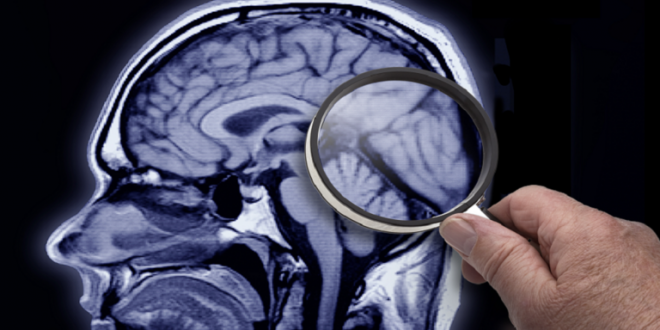

وأظهر تصوير دماغ المريض انكماشا في الحُصين، الذي يشارك في عمل الذاكرة، وألمح السائل الدماغي النخاعي إلى علامات شائعة لهذا النوع الأكثر شيوعا من الخرف.